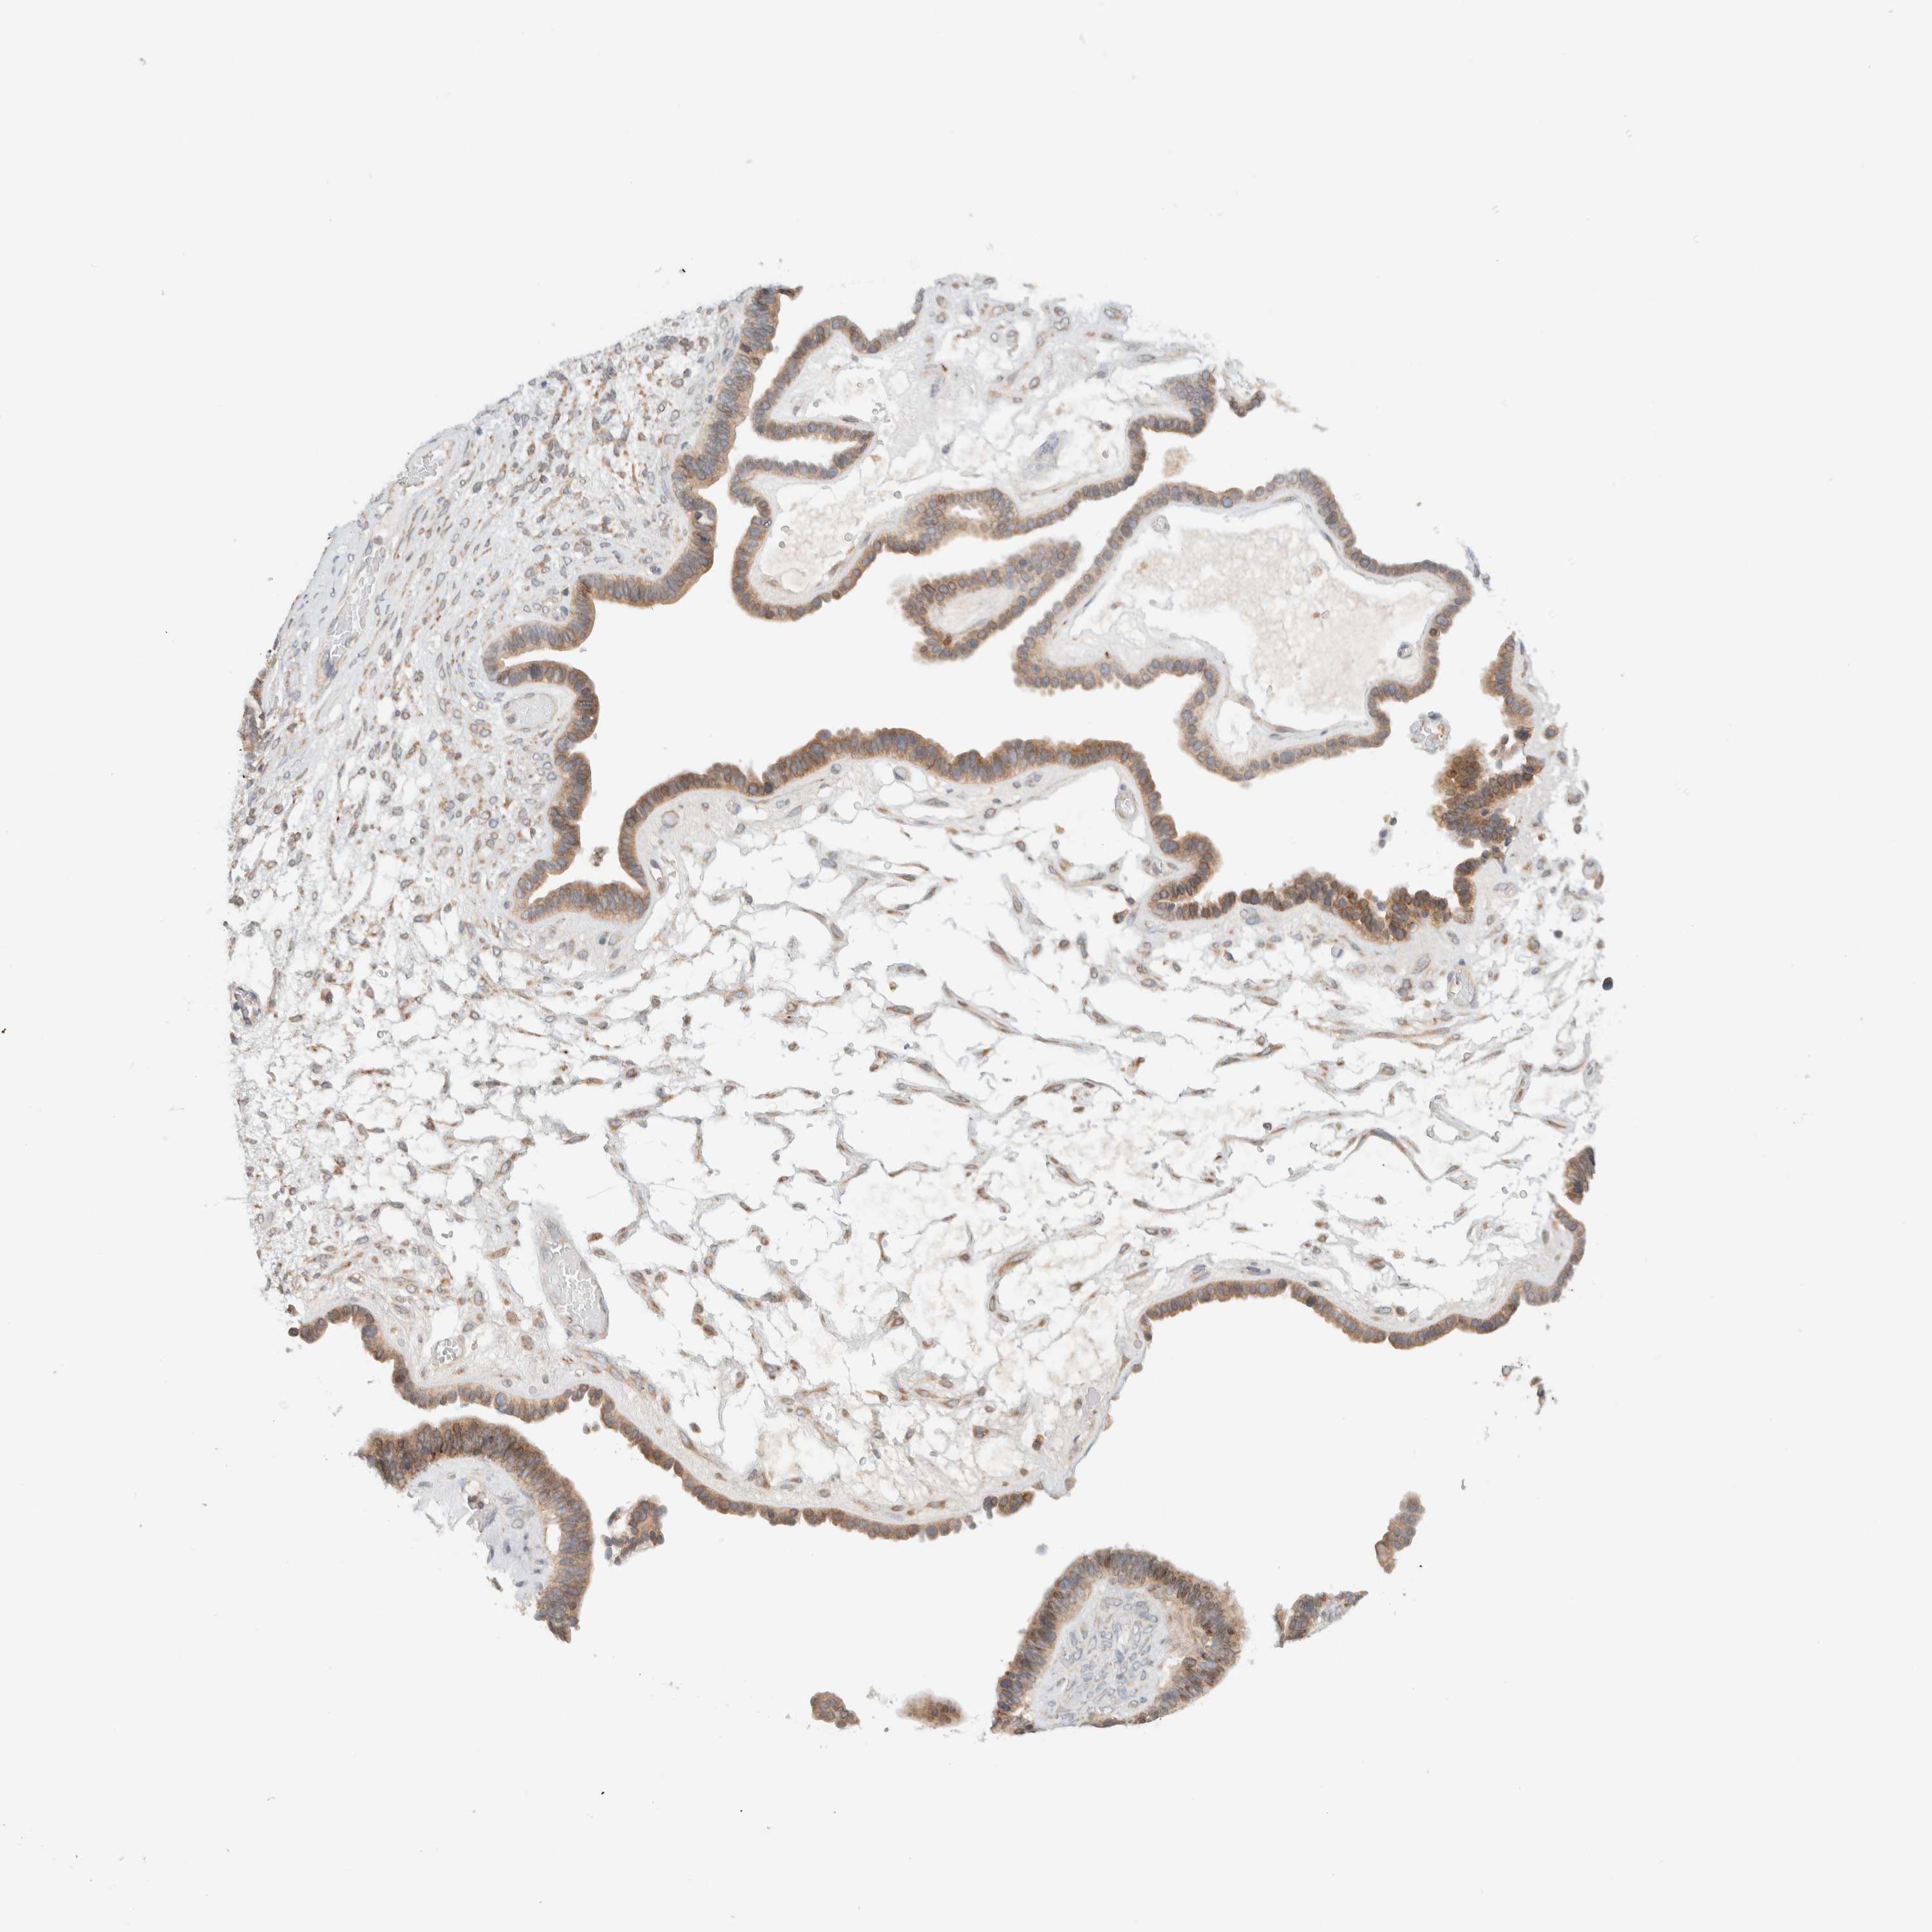

OVARIAN CANCER - Protein expressioni

A mouse-over function shows sample information and annotation data. Click on an image to view it in a full screen mode. Samples can be filtered based on level of antibody staining by selecting one or several of the following categories: high, medium, low and not detected. The assay and annotation is described here.

Note that samples used for immunohistochemistry by the Human Protein Atlas do not correspond to samples in the TCGA dataset.

Antibody stainingi

Antibody staining in the annotated cell types in the current human tissue is reported as not detected, low, medium, or high, based on conventional immunohistochemistry profiling in selected tissues. This score is based on the combination of the staining intensity and fraction of stained cells.

Each image is clickable and will lead to virtual microscopy that enables deeper exploration of all samples and also displays staining intensity scores, fraction scores and subcellular localization as well as patient and tissue information for each sample.

Antibody HPA021581

Antibody HPA023632

Staining

High

Medium

Low

Not detected

Intensity

Strong

Moderate

Weak

Negative

Quantity

>75%

75%-25%

<25%

None

Location

Nuclear

Cytoplasmic/membranous

Cytoplasmic/membranous,nuclear

Cystadenocarcinoma, serous, NOS

Carcinoma, endometroid

Cystadenocarcinoma, mucinous, NOS

Carcinoma, NOS